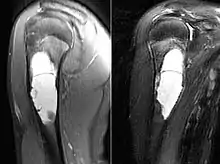

| MRI scan: simple bone cyst humerus of a 13 year old boy | |

Magnetic resonance imaging scans are used to identify the precise location of the cyst, to see how aggressive the disease is, and to determine the actual shape and size.[4] The MRI uses a combination of magnets and radio-frequencies to produce various detailed, computerized images of the cyst and its surrounding body structures.[4]